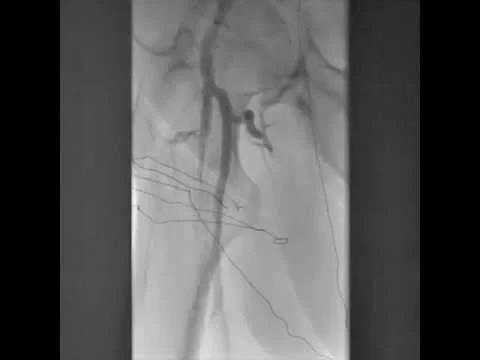

BTK CTO Viance & Enteer